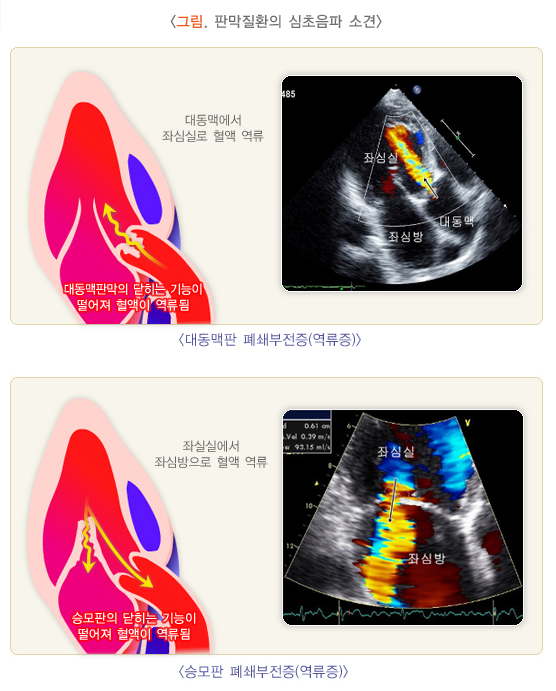

- 기본적인 심장 모니터링: **심전도 (ECG)**나 심장 초음파(Echocardiogram) 등을 통해 심장의 상태를 실시간으로 모니터링합니다. 이는 심장의 펌프 기능, 부정맥, 혈류 흐름 등을 파악하기 위해 중요합니다.

- 심장 초음파(Echocardiogram): 수술 후, 정기적인 심장 초음파 검사를 통해 승모판 기능, 심장 기능, 혈류 상태를 평가합니다. 판막 기능을 주기적으로 확인하고, 혈액 역류나 심장 크기 변화 등을 감지합니다.